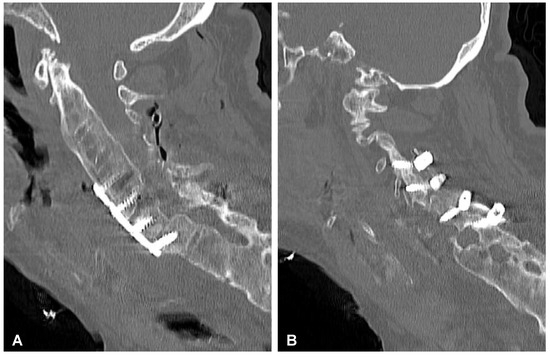

Figure 9. Postoperative sagittal CT scans (non-contrast enhanced) after the two-stage surgery of the cervical spine demonstrating placement of the anterior plate with locking screws (A) and posterior lateral mass screws (B) at the C4-C5-C6-C7 levels.

2.4. Surgery of the Cervical Spine Due to the Tetraparesis

Following the initial diagnostics, the patient was transferred to the operating room. The combined anterior and posterior osteosynthesis (360° fixation) at the C4-C5-C6-C7 levels were performed. In the first stage of surgery, the anterior stabilization plate (50 mm) and locking screws (Zephir; Medtronic, Minneapolis, MN, USA) under intraoperative 2-D fluoroscopy control were placed. In the second stage of surgery, the patient was turned and posterior-stabilized (Ellipse; Globus Medical, Audubon, PA, USA) with lateral mass screws (8 mm × 14 mm) using free-hand technique based on anatomical landmarks due to poor intraoperative visualization of cervicothoracic region capabilities using 2-D fluoroscopy was performed. A control CT scan performed one day after the operation revealed the correct placement of all the implants (Figure 9). After surgery, the patient remained in deep tetraparesis with minimal movements in the lower limbs but no movement in the upper limbs. Early postoperative rehabilitation at the bedside was initiated. However, the patient remained prolonged endotracheally intubated but was conscious and awake due to the retention of airway secretions, as well as was parenterally fed for 5 days. The patient was empirically administered intravenously with amoxicillin with clavulanic acid (1 g/0.2 g every 12 h). After successful extubation, the tracheostomy and percutaneous endoscopic gastrostomy (PEG) were not performed. After 12 days, the patient was discharged with no signs of infection and transferred to the rehabilitation center.